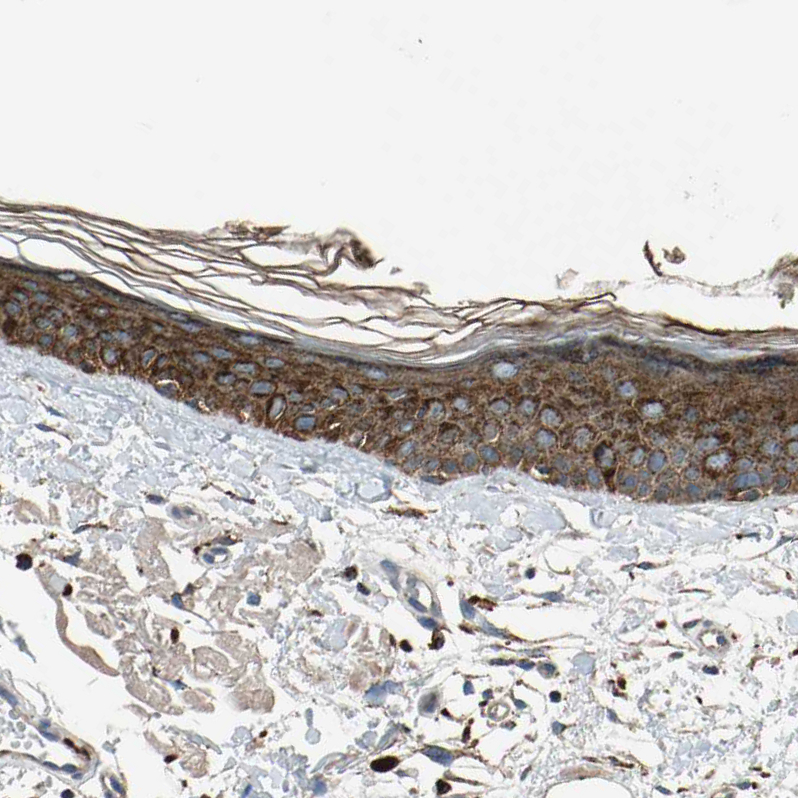

Immunohistochemistry analysis in human skin and skeletal muscle tissues using HPA008063 antibody. Corresponding GM2A RNA-seq data are presented for the same tissues.